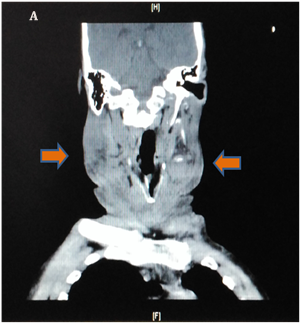

Ultrasound of the neck showed evidence of supraglottic edema, a finding that is confirmed by a computed tomography (CT) scan confirms supraglottitis and soft-tissue gas (Figure 1A & 1B). Leukocyte count was 36 x 103/mm3, and anion gap measurement indicates metabolic acidosis. After stabilization by administration of intravenous fluids and antibiotic agents, the patient was transferred to the operating room, where a drainage and cleaning of the anterior neck and floor of the mouth space was done through 3 incisions: two submandibular & one submental. Blood clots and necrotic tissues were optimally removed, tracheostomy was not indicated. The wounds were closed with drains (Figure 2A). Four days later, an additional drainage procedure was performed because of an infected fluid collection, and complete dental extraction was done. Patient was discharged in a good condition and at basal graft function (Figure 2B).

Figure 1: CT Skull, Neck & Upper Chest.